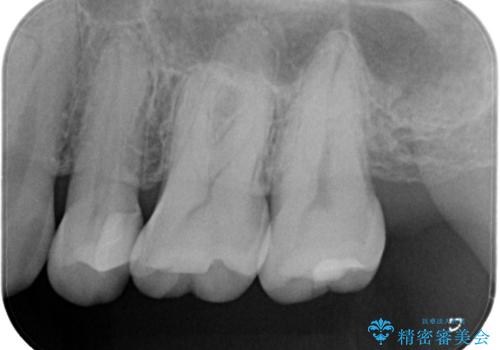

適合の良いセラミックインレー

- 定期検診して虫歯を認めたため、セラミックインレーにて修復治療を行なっております。

e-max プレスインレーにて修復治療を行っているため適合性及び審美性の高い治療を行うことができます